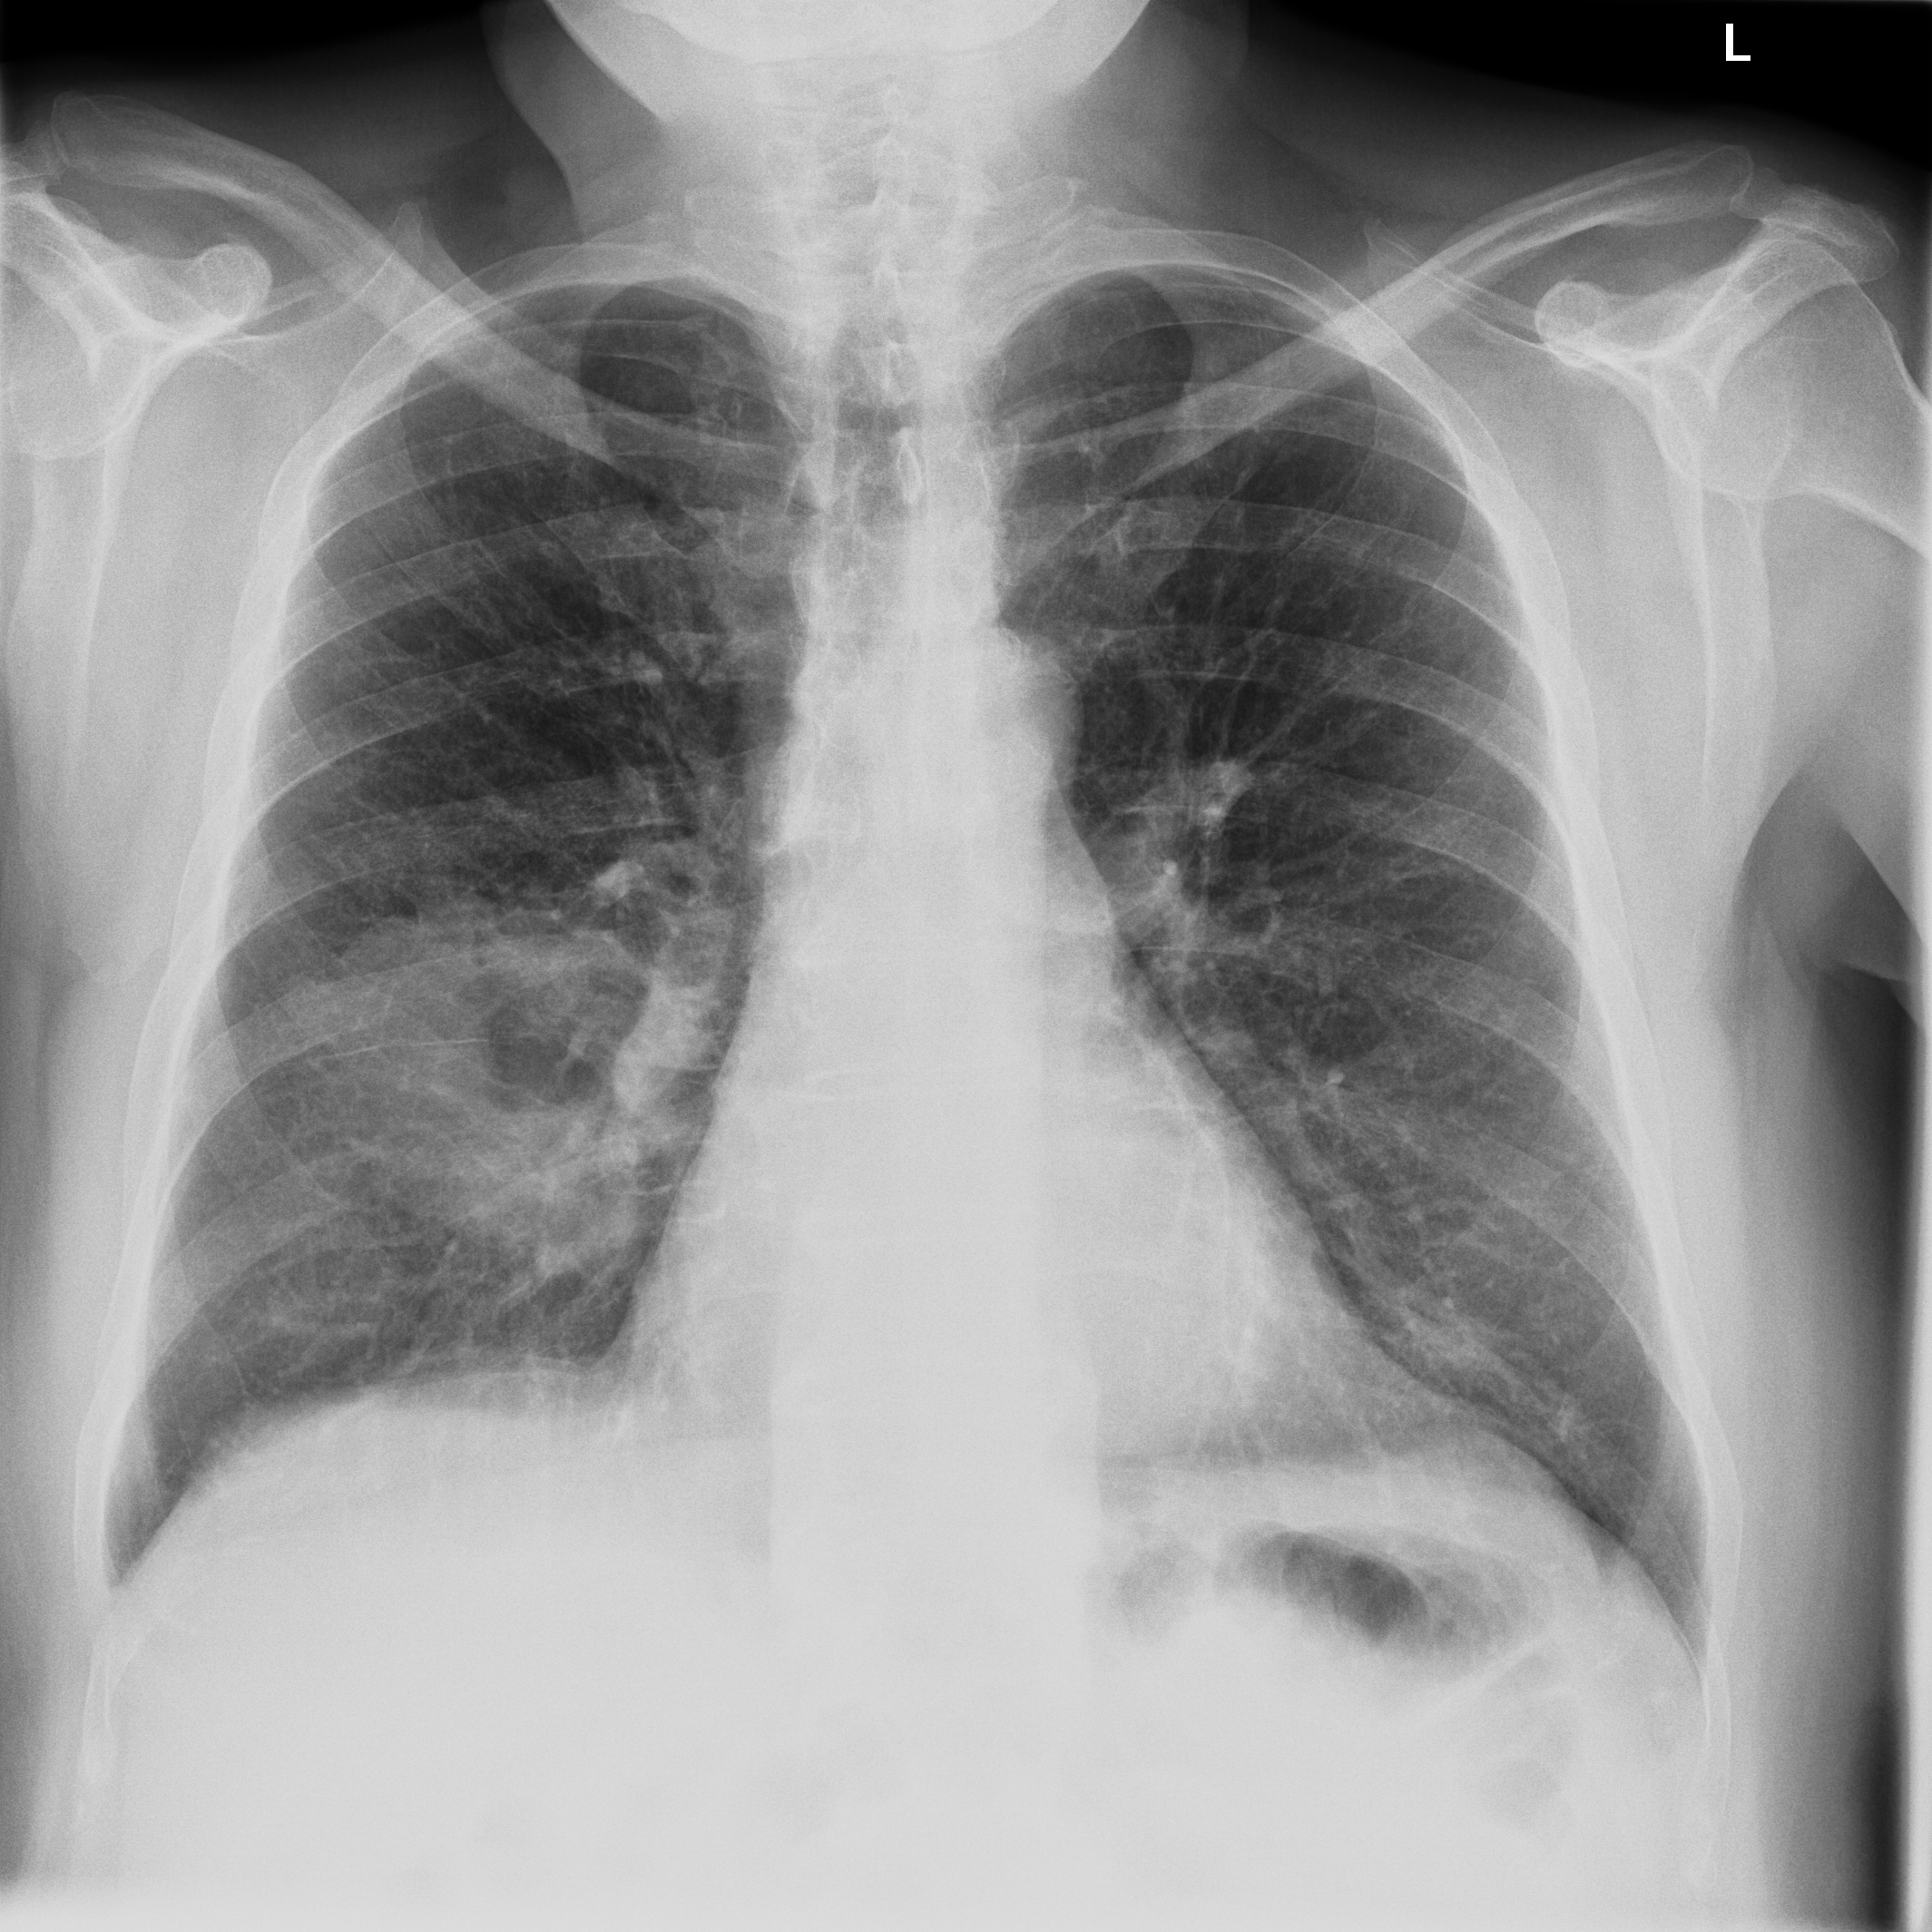

3.3.2 Data

Posteroanterior chest radiographs were acquired on two imaging systems (both Discovery XR656 HD models, GE Healthcare, USA) at Cambridge University Hospitals NHS Trust. Each scanner was being set up in the hospital with different post-processing parameters (chosen by the operating radiologists), which are used here as reference images, see Figure 7 and 8(a). Additional images, serving as real-life examples of lower quality, were produced for each radiographic exposure using multiple different post-processing settings. The post-processing was applied in the hospital directly on the scanner itself by adjusting parameters in the provided framework.

Refer to caption

(a) Reference

(b) (21.1, 0.90, 0.11)

(c) (19.5, 0.88, 0.16)

Figure 7: Chest X-Ray scans with different kinds of post-processing; (a) serves as reference and (b) is wrongly judged as better visualization by PSNR/SSIM/LPIPS.

FR-IQA mismatches

In Figure 7, contrast deviation and edge enhancement were reduced in (b), but increased in (c), the noise reduction algorithm was removed in both. The brightness was increased in both images but more so in (c) and low-contrast enhancement was removed in (b). The result is that (b) has relatively low contrast in the lungs compared to the reference (a) and radiograph (c). In Figure 8, edge enhancement has been dramatically increased in (b), whilst the contrast deviation and tissue contrast have been reduced. In (c), the brightness, tissue contrast and edge enhancement have been slightly increased. Consequently, (b) provides low contrast in the lungs with excessively prominent lung markings and vasculature which make it harder to detect abnormalities such as a pneumonia.

All of the chosen FR-IQA metrics wrongly judge (b) as the better image in the first example Figure 7, and the results in (b) and (c) of the second example Figure 8 are quite close, where PSNR and SSIM are also providing the wrong order. The tested measures are not suitable to evaluate the quality of data sets with X-Ray images that have large variations regarding contrast, luminance and sharpness.